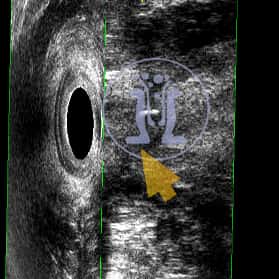

Ασθενής γυναίκα με φλεγμονή στο πεπτικό, προσέρχεται με αδυναμία στην συγκράτηση των κοπράνων. Στο ιστορικό της αναφέρει εγχείρηση με την μέθοδο του Ιπποκράτη. Ανευρίσκονται μετεγχειρητικές αλλοιώσεις του έξω σφιγκτήρα.